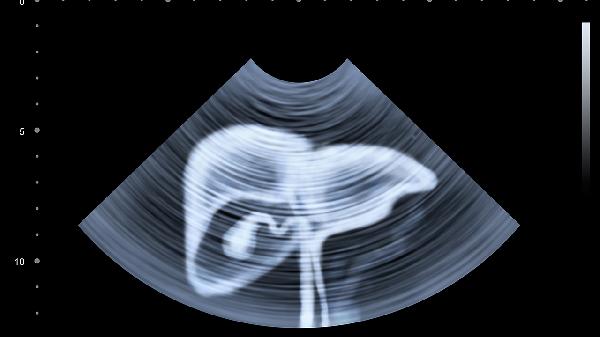

肿瘤:常见的妇科恶性肿瘤有子宫颈癌、子宫内膜癌和卵巢恶性肿瘤等。